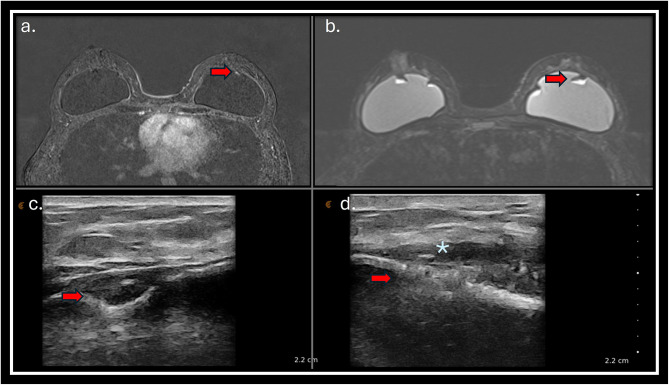

Materials and methods: A prospective observational study was conducted in a single center to evaluate breast implant complications in patients referred to breast magnetic resonance (MRI) scan. All patients who had breast implants submitted to MRI scan were invited to a complementary dedicated ultrasound (US) evaluation of the breast implants. The implant changes were classified following a dedicated protocol. The classifiers used to evaluate the implant include evaluation of implant surface (shell), implant internal content homogeneity, fibrous capsule, intracapsular space, pericapsular space, and axillary extension.

Results: Preliminary results included evaluating 29 consecutive patients who underwent MRI. Twenty-nine patients with 49 implants were included in the study. The US showed a superior ability to assess the internal contents of the implants, the implant surface, and the intracapsular contents. There were no significant statistical differences in evaluating macro changes such as implant location, intracapsular collection, and radio-frequency identification (RFID) presence. MRI was superior to the US in classifying the fibrous capsule type.